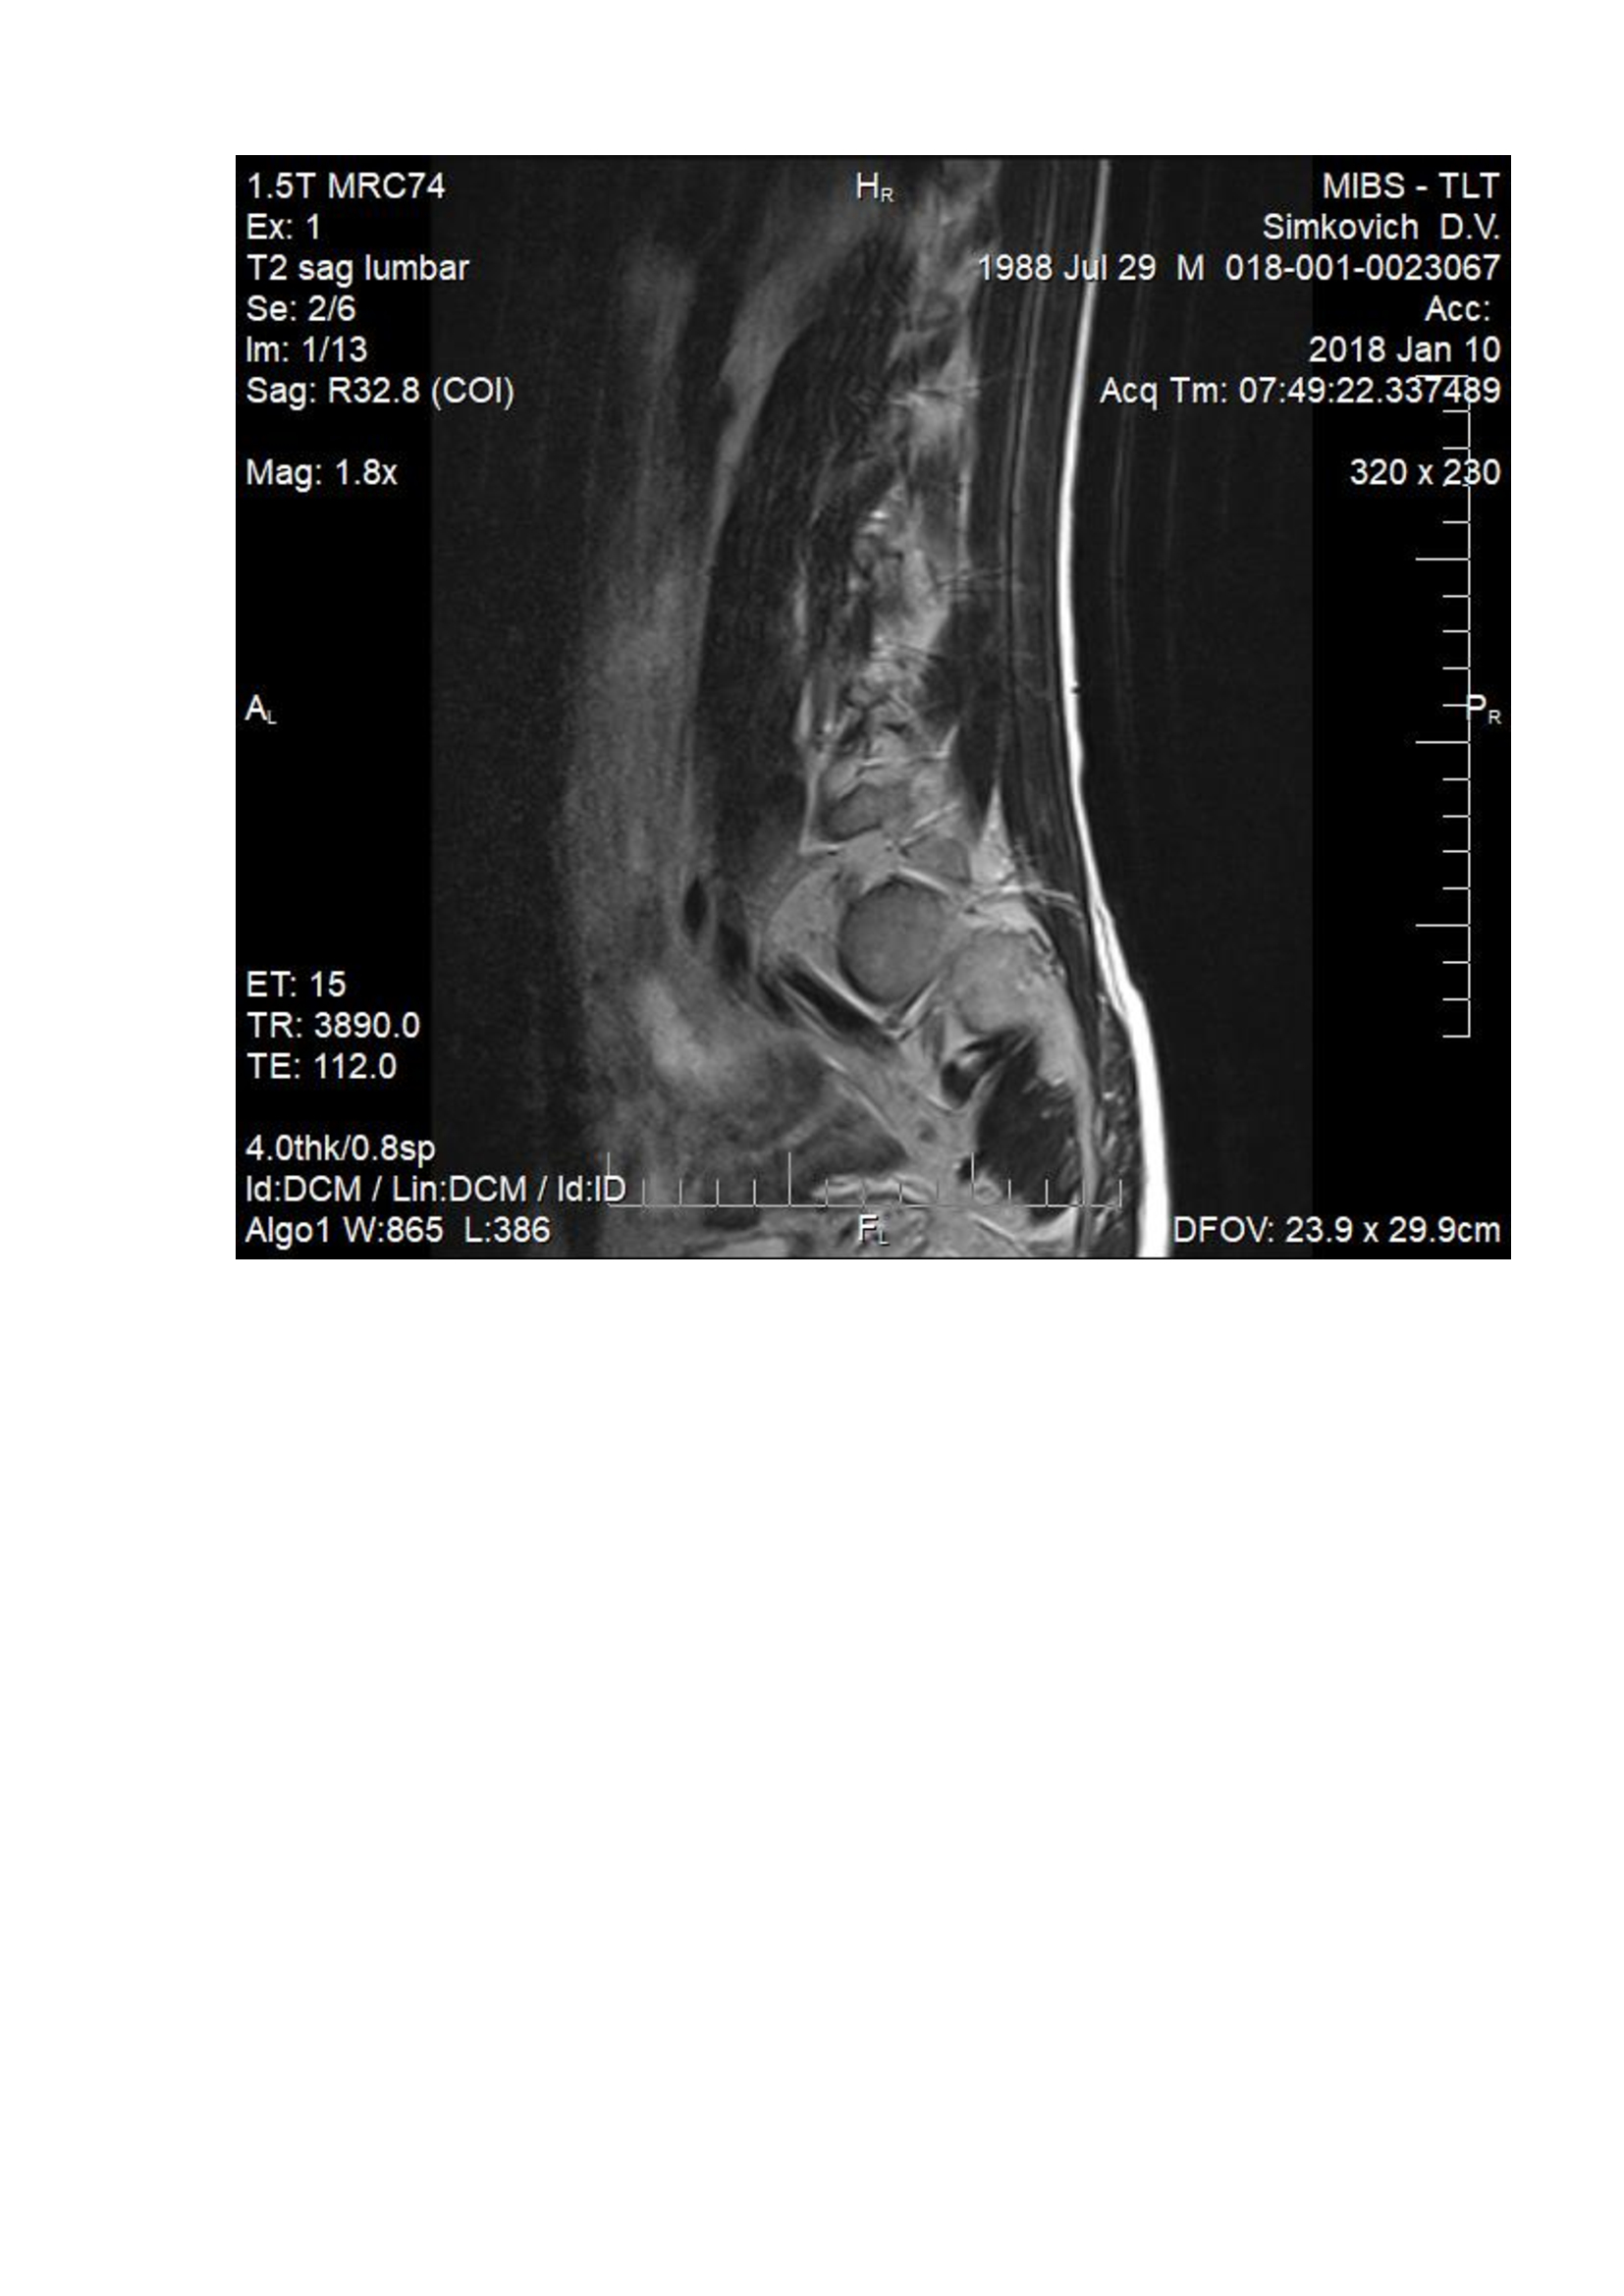

На данный момент болит правая нога, начала побаливать и левая, болит спина. При лежании на спине на ровной поверхности боль в спине проходит. Сделал МРТ. Неврологи нашего города ставят разные диагнозы, от фасеточного синдрома до нестабильности позвоночника. Консервативное лечение не помогает.

Посмотрите пожалуйста мои снимки.

Здравствуйте! судя по снимкам -грыжа удалена. Для определения формирования рубцово-спаечного процесса - мы делаем мрт с в/в контрастом, для определения нестабильности - обычный рентген с функциональными пробами, для определения степени поражения нерва ЭНМГ нижних конечностей. Далее становится понятно в какую сторону двигаться.